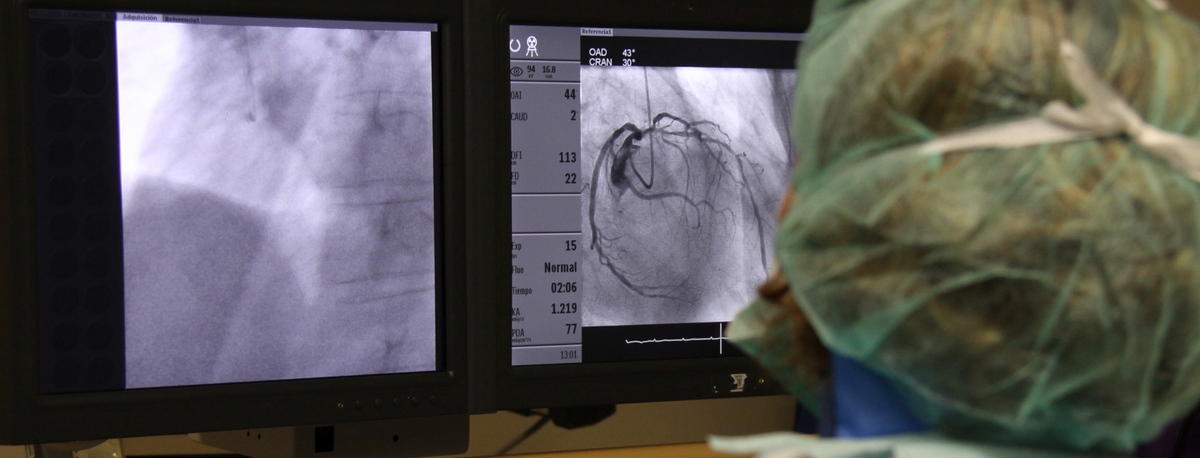

Teknon Cardiology Institute

The institute is staffed with specialists in angiology, vascular surgery, and endovascular surgery, who handle everything from diagnosing to monitoring circulatory system illnesses.Cerebral embolism and pulmonary thromboembolism are some of the leading causes of death due to vascular problems.

Our team specialises in minimally invasive techniques, using endovascular techniques without surgery, which allow vascular prostheses to be implanted to resolve dilations or aneurysms of the arteries. We also offer all treatments for venous and peripheral arterial disease, including carotid artery disease.